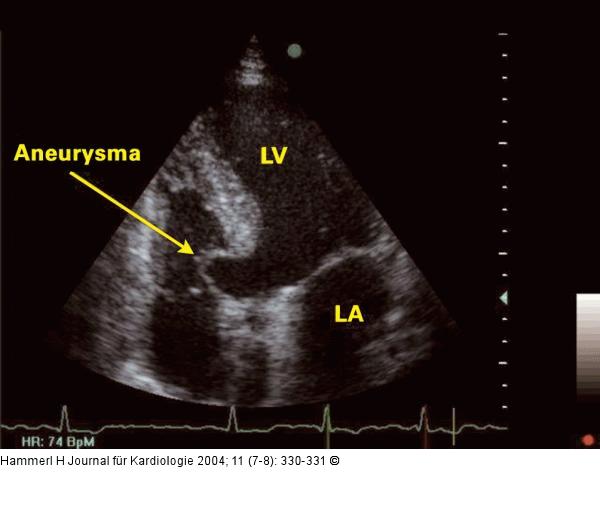

Abbildung 1: Interventrikuläres Septum - Aneurysma Apikaler Vierkammerblick: Aneurysma des interventrikulären Septums; LA = linker Vorhof; LV = linker Vorhof |

Apikaler Vierkammerblick: Aneurysma des interventrikulären Septums; LA = linker Vorhof; LV = linker Vorhof |